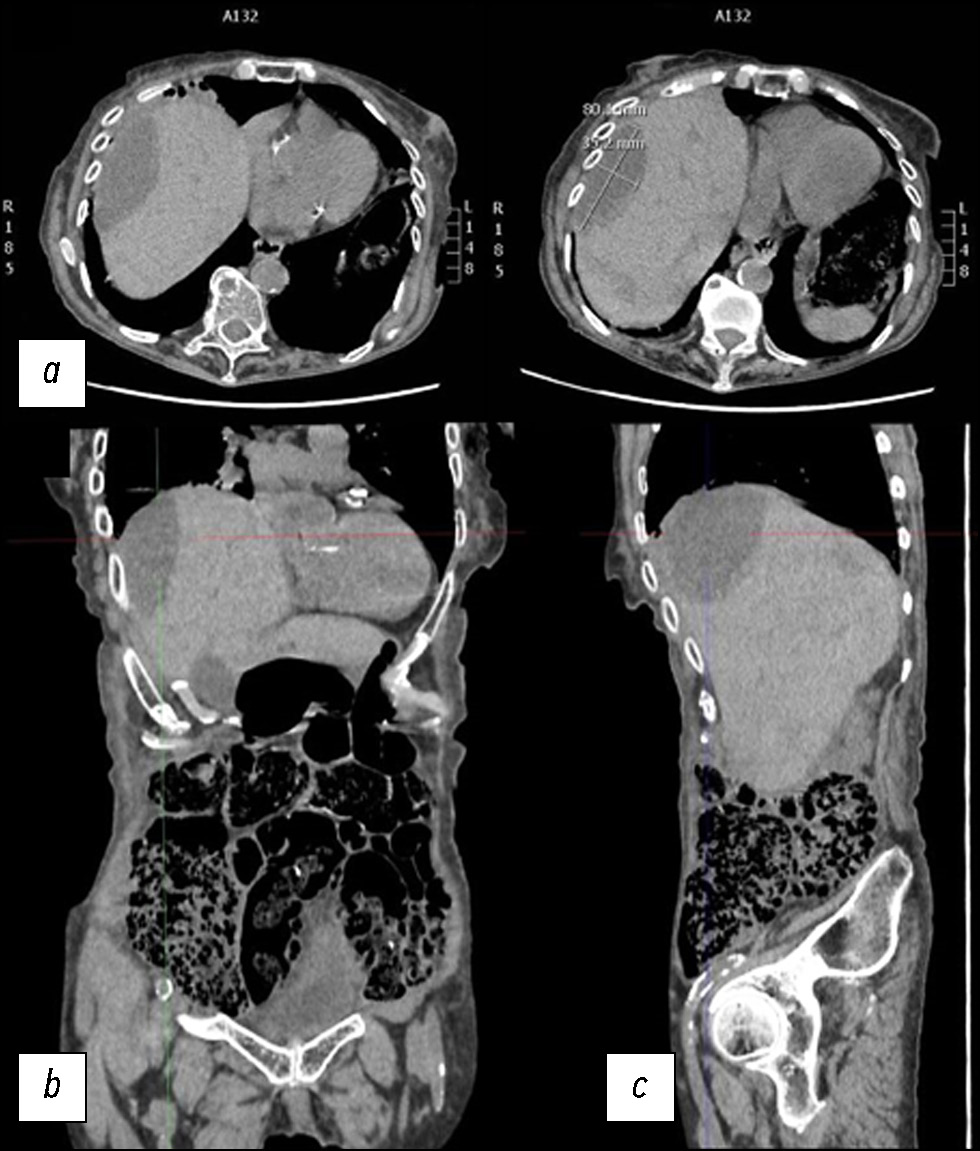

A case of spontaneous liver rupture and the role of imaging: from computed tomography to interventional treatment

Abstract

Hepatic parenchymal rupture is a rare but potentially fatal condition that can be caused by trauma, iatrogenic factors, spontaneous causes, etc. This case report describes the diagnostic and therapeutic steps employed in a patient with spontaneous hepatic parenchymal rupture. An older woman came to the emergency department with diffuse stomach pain. After clinical evaluation, she underwent computed tomography. The first computed tomography did not reveal a full-blown parenchymal rupture. Owing to data ambiguity, indicating that the abdominal discomfort could be caused by renal or biliary colic, obtaining an early diagnosis was very difficult. In truth, only few hypodense oval shapes with characteristic suprafluid densitometry were found in the liver parenchyma. However, after a few days, the discomfort persisted, and as the condition worsened, the patient underwent additional radiological examinations, which revealed the rupture of the liver parenchyma that required arteriography, and a long hospital stay until clinical resolution.